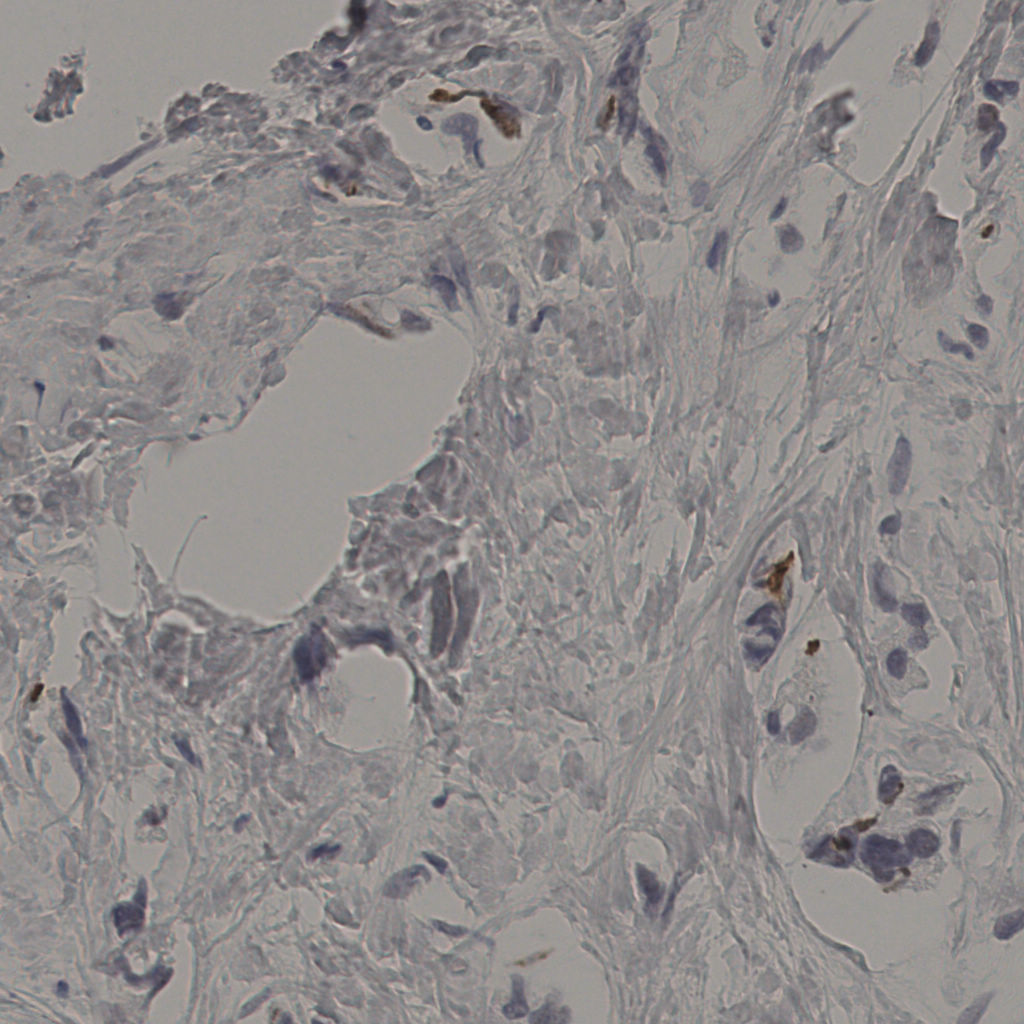

5.31%

Ki67 指数

阴 19502

阳 1093

切片统计

总切片

2970

有效

554

已标记

554

有效率

19%